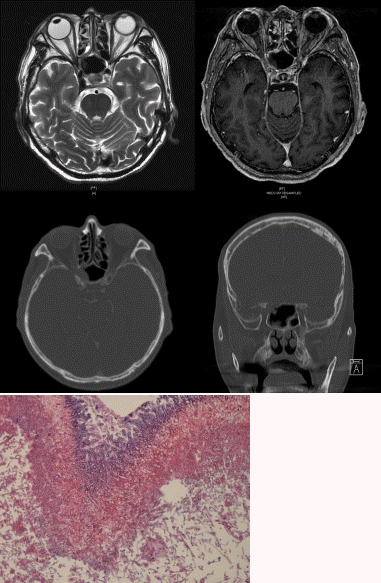

72세 남자 환자가 우측 시력저하를 주소로 시행한 접형동의 병변을 주소로 의뢰되었다. 과거력상 당뇨로 투약 중이며 직장암으로 수술 시행 후 항암치료 중이었다. 항암 치료 위해 입원 시 수개월 전부터 진행된 우측의 시력 손상으로 evaluation 위해 시행한 brain MRI와 paranasal sinus CT상 아래와 같은 소견을 보였다. 접협동 내의 병변 제거 후 시행한 병리 검사상 아래와 같은 소견을 보였다. 다음 환자에서 가장 적절한 치료는?

해설 만성침습성진균성부비동염(chronic invasive fungal sinusitis)로 급성전격성진균성부비동염에 비하여 진행이 느리고 괴사가 덜한 것이 특징이다. Aspegillus fumigatus가 가장 흔한 균주로, 진균의 점막 침범과 림프구, 거대세포, 육아종이 침윤 등이 관찰되며, 주위 골조직을 미란시켜 안구나 두개낭 내로 감염을 확산시키기도 한다. 치료는 병변부위의 광범위제거 및 전신적인 항진균제인 amphotericine B를 수주간 사용하는 것이며, 급성의 경우에 비하여 예후는 양호하나 재발이 드물지 않아 주기적인 단층촬영과 내시경검사를 요한다.